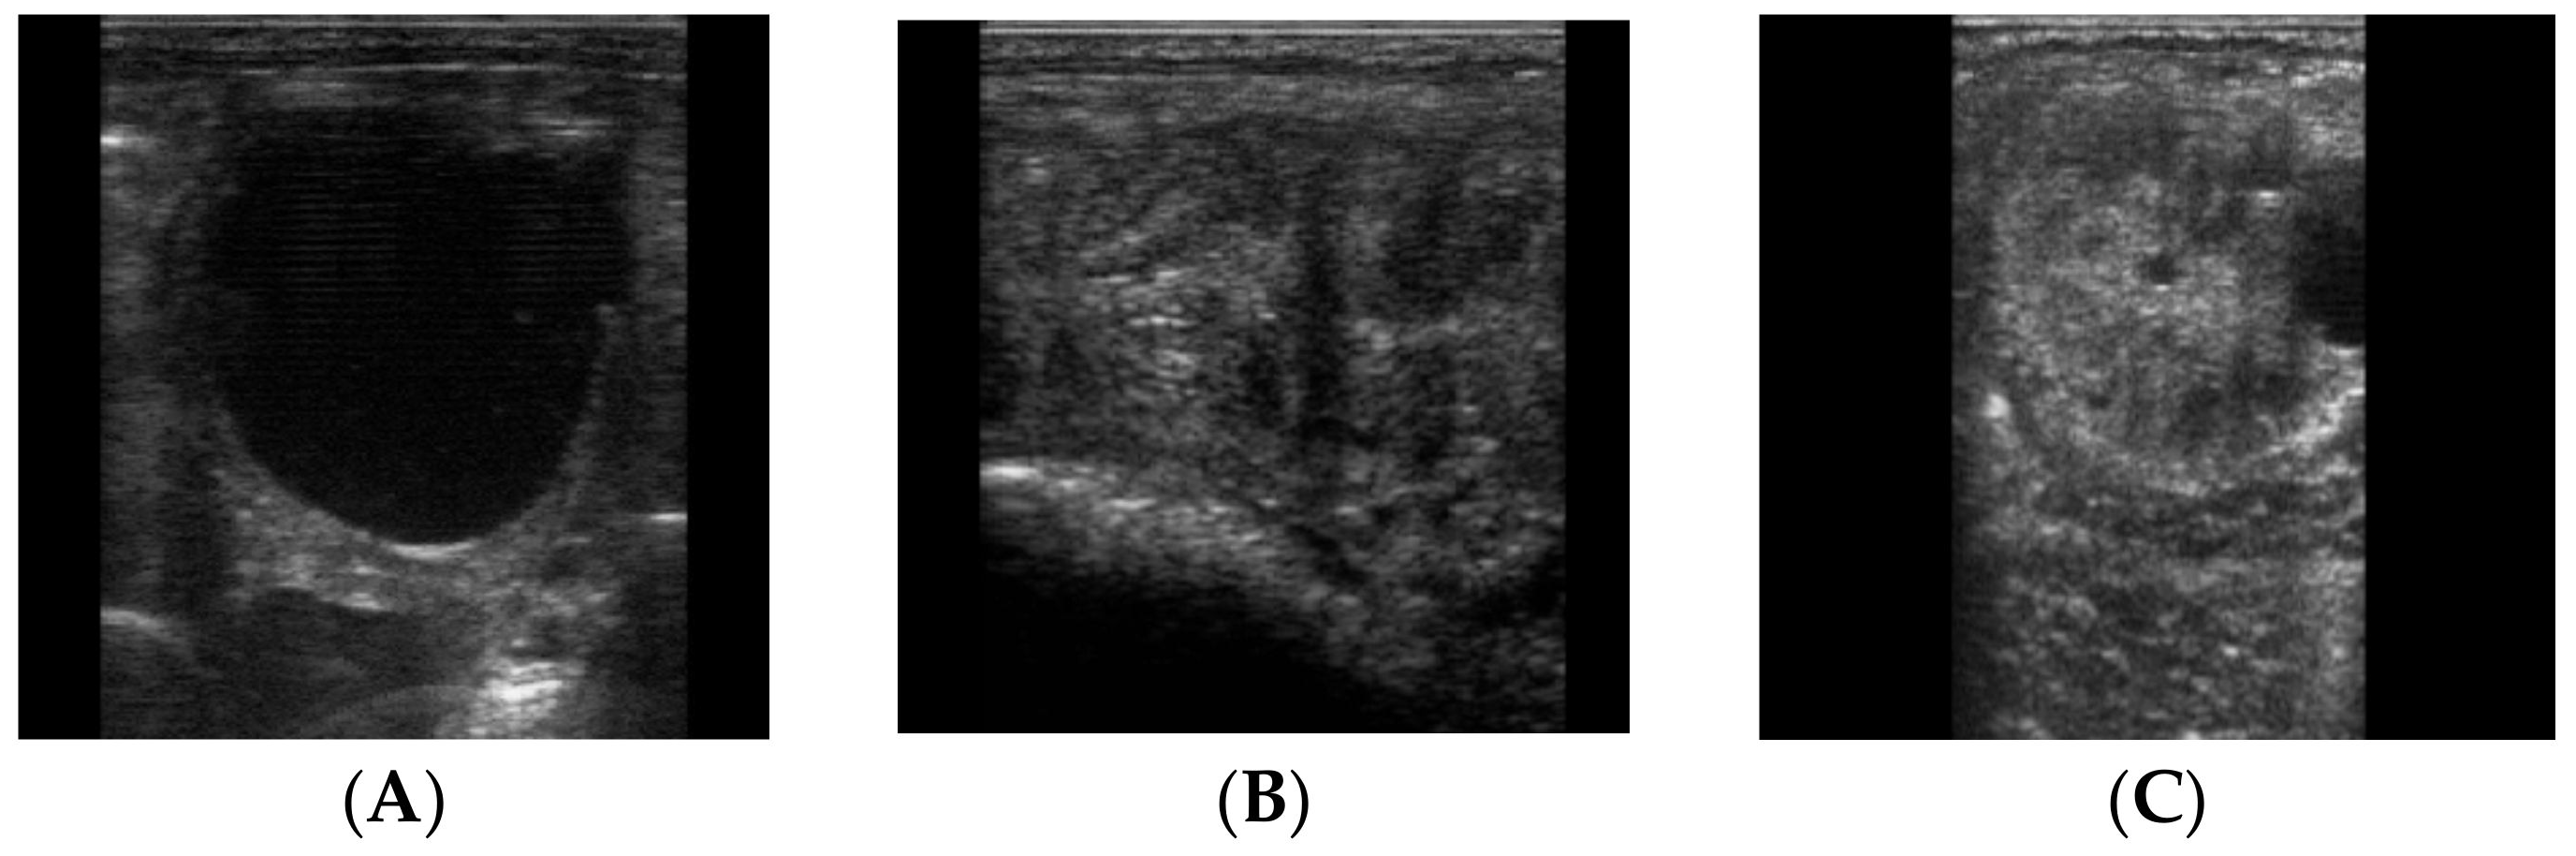

2.2. Samples Collection